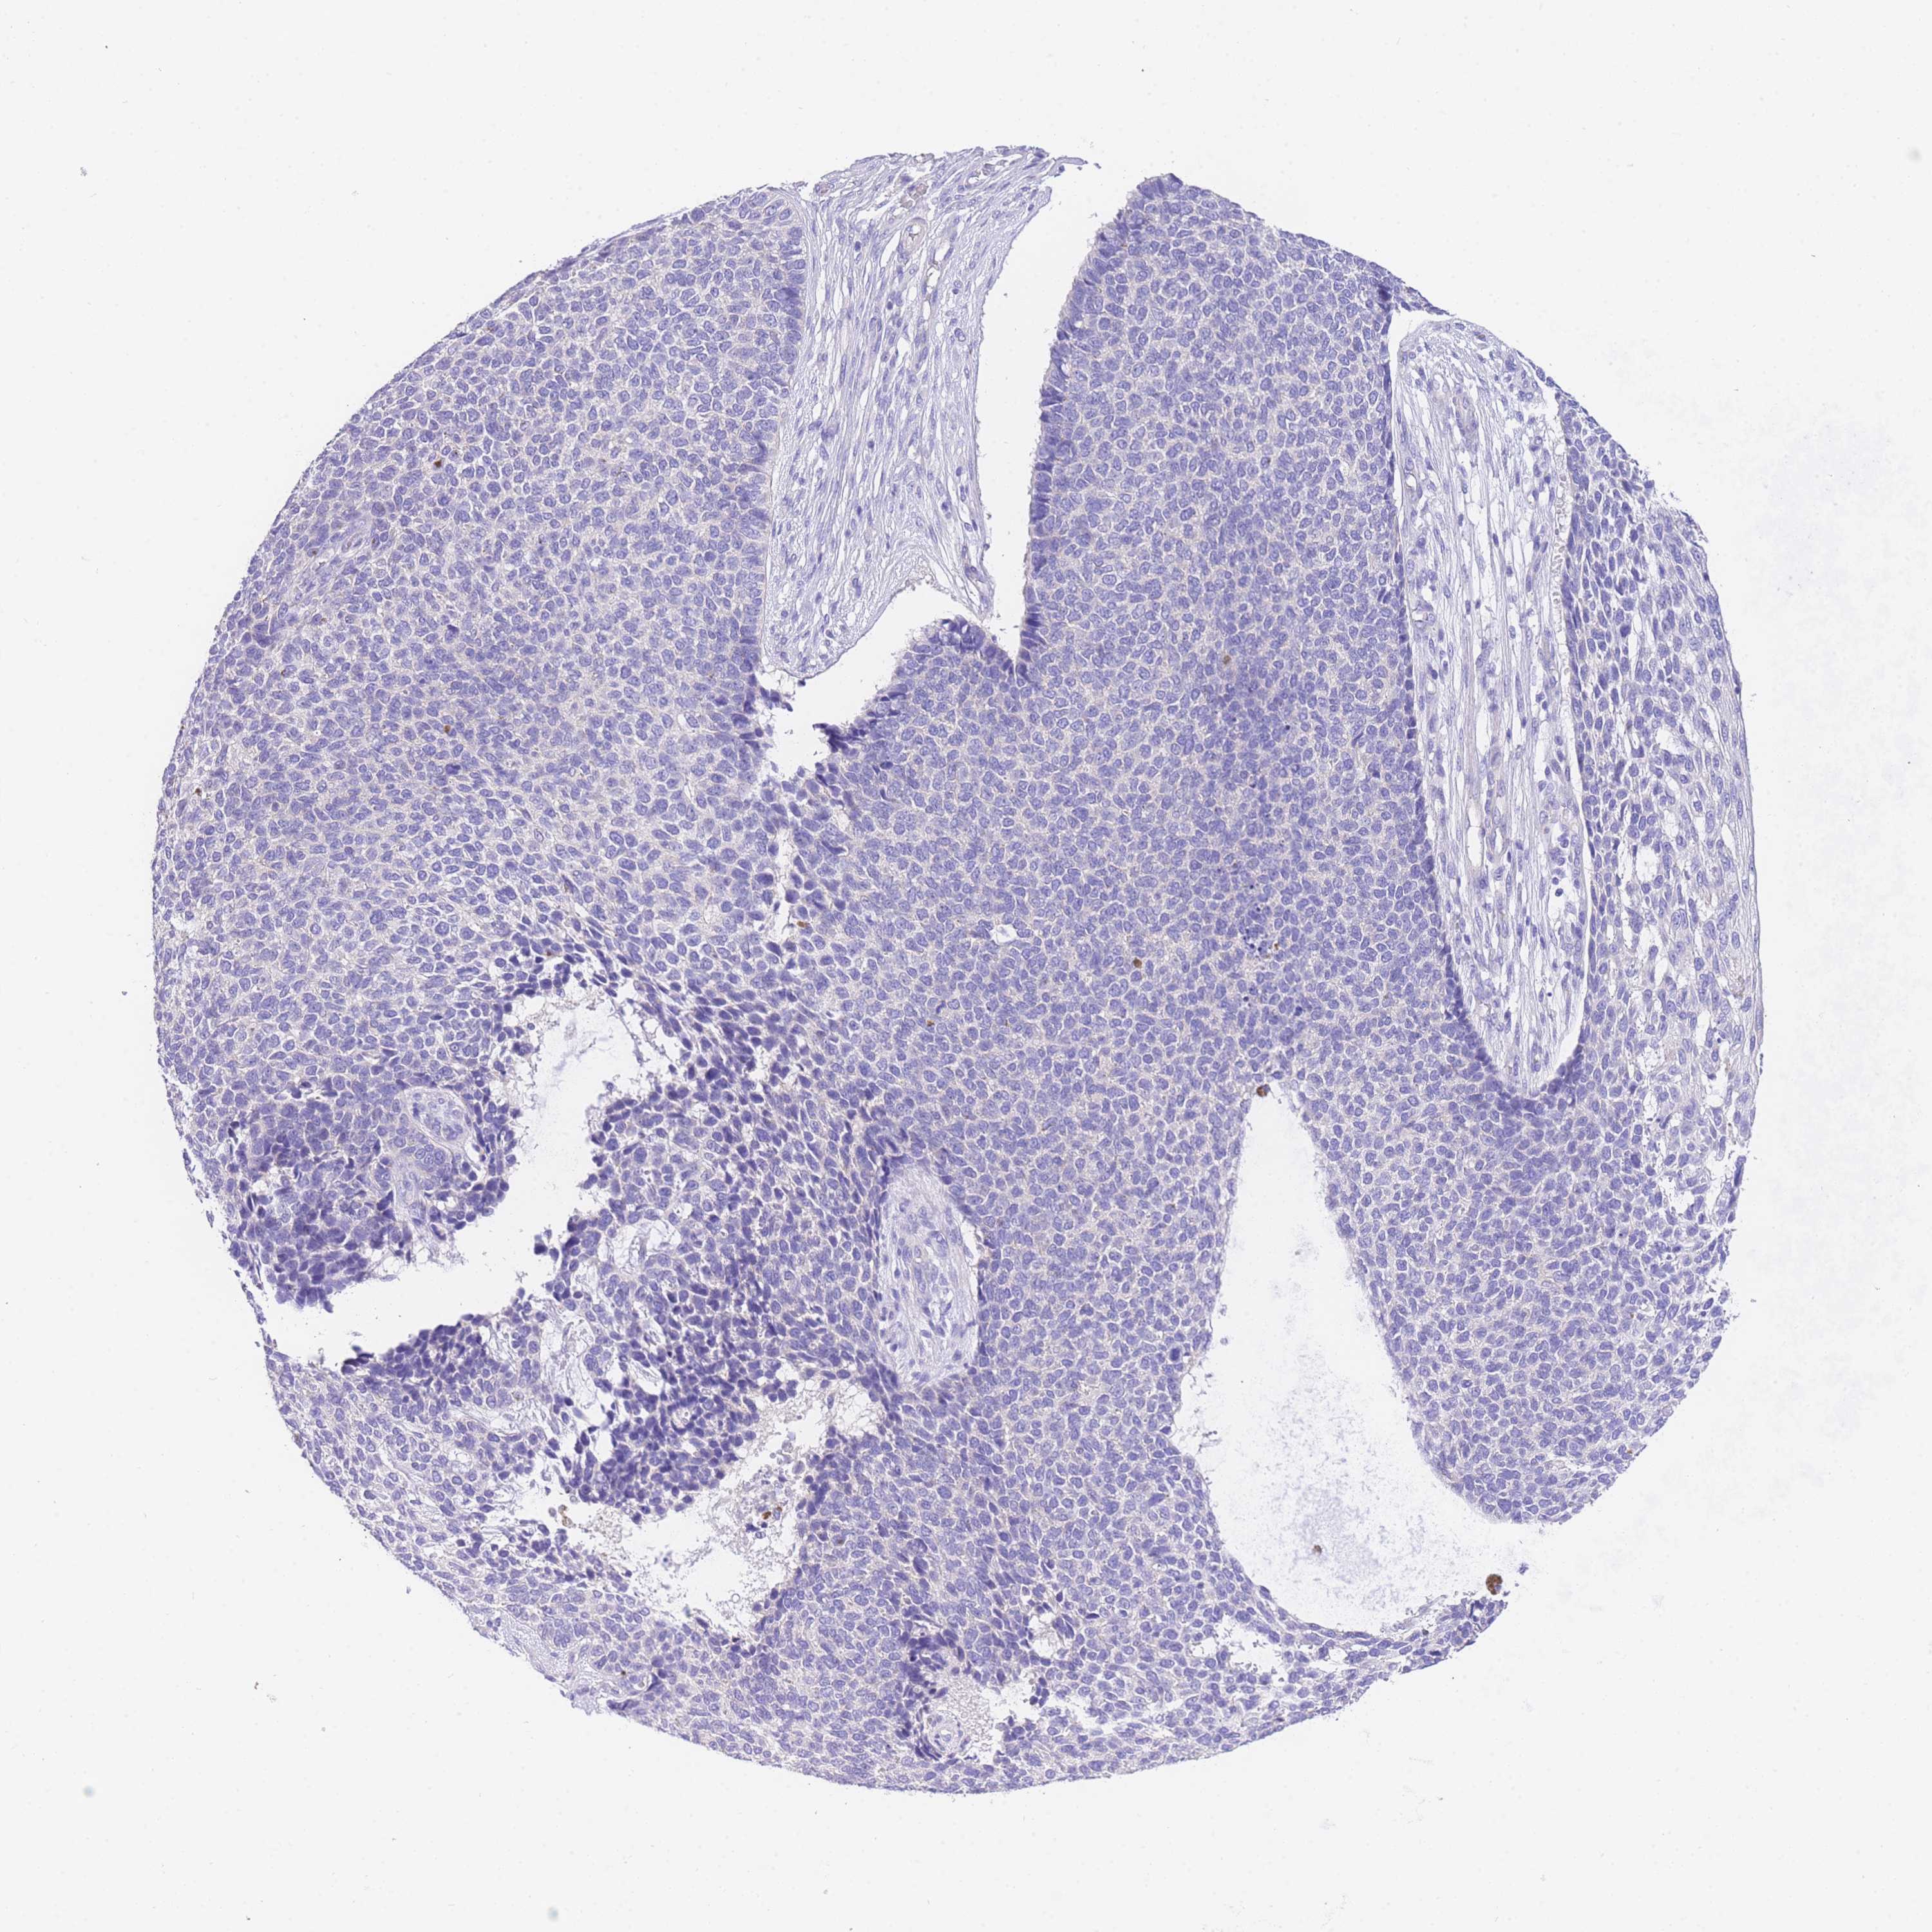

Basal cell and squamous cell cancer

SKIN CANCER - Protein expressioni

A mouse-over function shows sample information and annotation data. Click on an image to view it in a full screen mode. Samples can be filtered based on level of antibody staining by selecting one or several of the following categories: high, medium, low and not detected. The assay and annotation is described here.

Each image is clickable and will lead to virtual microscopy that enables deeper exploration of all samples and also displays staining intensity scores, fraction scores and subcellular localization as well as patient and tissue information for each sample.

Antibody HPA049809

Basal cell carcinoma

Squamous cell carcinoma, NOS

Squamous cell carcinoma, metastatic, NOS